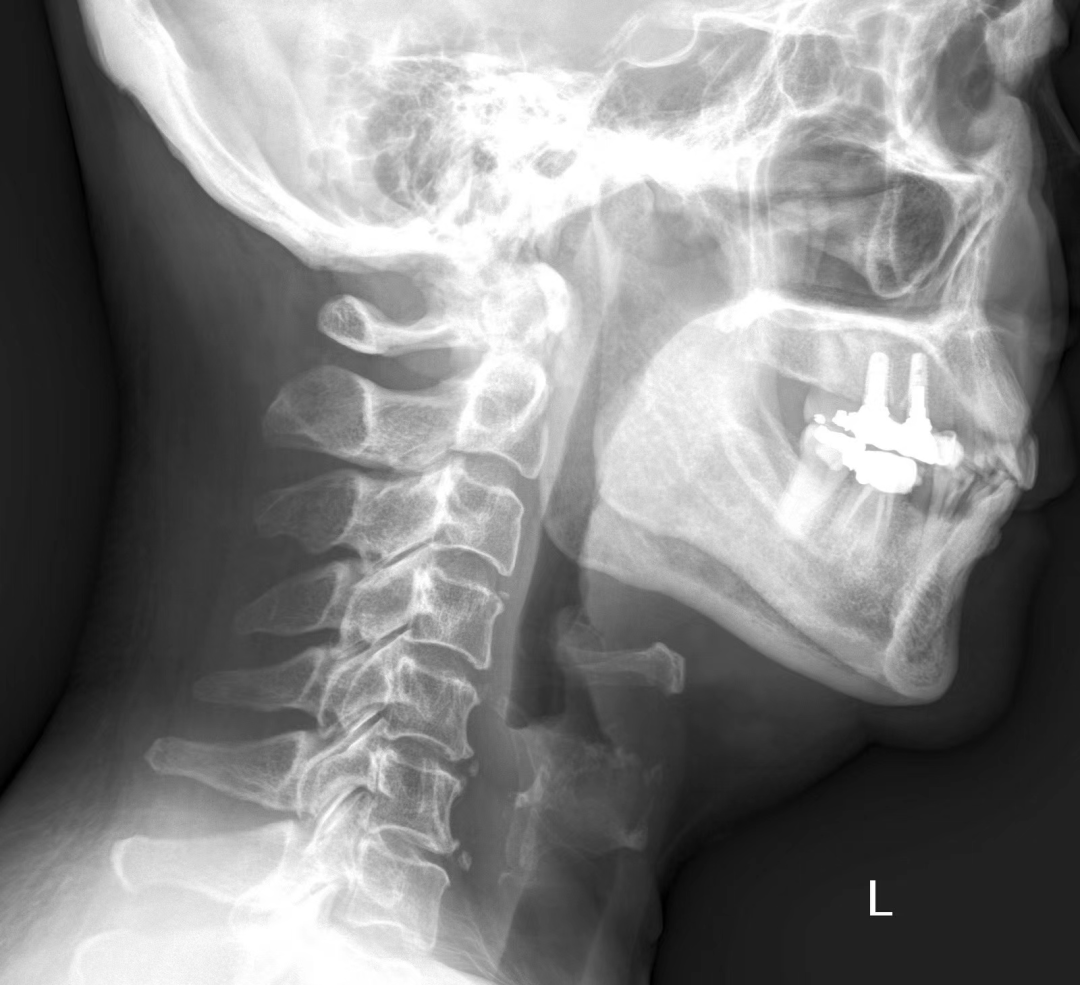

为啥小小的鱼刺,到了国外就找不着也拔不出了呢?中国医生咋就那么会拔鱼刺呢?中国医生厉害的拔鱼刺技术,根本原因是中国人吃了太多「鱼刺」。说起吃鱼,中国人想到的更多是剁椒鱼头、糖醋鲤鱼,还有妈妈熬的那碗鲫鱼豆腐汤。它们有一个特点:都是淡水鱼,刺多。而欧美国家更多食用的是海洋鱼类。海水鱼与淡水鱼的主要区别之一就是缺少肌间骨,也是吃鱼会不会卡鱼刺的关键。这是 X 光下的一条淡水鱼。肌间骨是那些 I 字形、Y 字形的小刺,是一次次把我们送去急诊室的罪魁祸首。欧美地区很少吃淡水鱼,留给欧美医生实践处理小鱼刺卡喉的机会实在是太少,操作经验不足且不灵活。以美国为例,全部消化道气道异物发生率不高,小孩子的异物多数是硬币,成年人多数是肉块或者鸡骨,鱼刺占比低到基本不统计。这就决定了他们的卡鱼刺处理策略,还是沿袭大块异物诊治流程,提倡首先通过 X 光、CT 等影像学检查确定位置。然而影像学观察小鱼刺难度很大,大量的时间浪费在「找刺」上。就算找到了,拔鱼刺也不怎么熟练。因此在美国拔一根鱼刺真就有可能折腾十几个小时。5 年来,仅仅是发表的特殊案例数量就有 24529 例,真实发生的鱼刺卡喉数都数不过来。很多医院一晚上急诊都能处理两位数的鱼刺卡喉,节假日还会翻倍。面对这样的现实,中国医生在处理鱼刺方面必须要更快、更精准。中国医生通常会绕开 X 光等检查的步骤,借助于更为熟练掌握的各种喉镜技术直击痛点,并且在取异物器材方面推陈出新,一切都为了更快的搞定鱼刺,减少痛苦。一批批一代代医生的努力和实践,让一根鱼刺在中国的急诊不再是多学科疑难杂症,而是值班医生的驾轻就熟。普通的鱼刺,坐下→张嘴→好了,最快几分钟就解决了。海量的患者需求,最终造就了中国医生精湛的鱼刺处理技艺。中国拔鱼刺主力是急诊耳鼻喉医生,口腔和消化科医生则负责处理少数不走寻常路的鱼刺。如果你卡了鱼刺去往急诊,接待你的大概率会是耳鼻喉科医生。一般情况下,医生不会让你去做 X 光等其他检查,只需要坐好在诊室里,张开嘴巴。少数鱼刺会卡在扁桃体表浅处或舌背上,张嘴就能看到。没有看到的话,就要压住舌背,借助于间接喉镜观察。那个亮亮的小镜子就像潜艇的潜望镜,可以扩大视野,看清楚直视看不到的地方。如果还是没有看到,刺入更深,会使用真正的电子喉镜,从鼻腔进入咽喉仔细探寻。容易看到的那些鱼刺,拔出也相对容易,一根镊子就能又稳又准地解决问题。更深部分的鱼刺,就要借助于更犀利的工具从内镜过去拔鱼刺。为了拔得更顺手,中国医生还推动了异物抓取钳的改进,从简单的单一样式发展到今天的五花八门。这些形形色色的异物抓取钳,适合用来处理不同直径、不同位置的鱼刺。粗的、细的,深的、浅的,上面的、下面的……没有鱼刺能轻松逃过中国医生手里的抓取钳。如果鱼刺不幸刺入食管或者更深处的胃,处置原则也是一样的,只是操作用内镜从喉镜换成胃镜而已。总之不管用什么手段,鱼刺都逃不出中国医生的手掌心。注:费用参考来源于多地不使用电子喉镜时的基础收费,请以实际情况为准。特殊情况下,医生也有可能为了安全先安排 X 光等检查。虽然中国医生很会拔鱼刺,但仍有很多鱼刺成为了我们的健康大患。有些鱼刺扎得实在太深,穿透咽喉或者食管壁,刺破身体内部,那就糟糕了。拔鱼刺专家们给到大家一些原则:有选择的话,尽量少吃有小刺的鱼;吃鱼时专心致志剔鱼刺,别看剧别说话;能单独吃鱼,就别混在米饭里一口吞;卡住了尽快去医院,别用醋和馒头的土方法自救。还要谢谢生物学家们,他们正在利用基因技术研发没有肌间骨的淡水鱼。未来如果大规模上市,大口吃鱼就更有底气,各家医院的夜间鱼刺门诊可能就要撤销了。不过中国医生这门手艺可能还不会放下,因为除了尖锐的鱼刺卡喉,还有另外一种刺入食管的尖锐异物——枣核,也是急诊常客。希望生物学家们什么时候也惦记一下。致谢:本文经中国科学技术大学附属第一医院耳鼻咽喉科主治医师 潘春晨 专业审核[1]中国科学报:10 年做出原始创新成果!无小刺鱼诞生全揭秘[2]中华医学会消化内镜学分会. 中国上消化道异物内镜处理专家共识意见(2015年,上海). [3]Kim HU. Oroesophageal Fish Bone Foreign Body. Clin Endosc. 2016 Jul;49(4):318-26. doi: 10.5946/ce.2016.087. Epub 2016 Jul 26. PMID: 27461891; PMCID: PMC4977739.[4]https://www.entclinic.sg/blog/fish-bones-in-the-throat/[5]Wei X, Wang J, Xu W. Emergency management of jujube pit esophageal impactions using rigid esophagoscopy in the aged[J]. Laryngoscope Investigative Otolaryngology, 2021, 6(6): 1332-1338.[6]马良骁, 董在杰, 苏胜彦, 等. 鱼类肌间刺的研究进展[J]. 江苏农业科学, 2012, 40(4): 234-235.丁香园是面向医疗从业者的专业平台,以「助力中国医生」为己任。下载「丁香园 App」可以和同行讨论病例 ,在线学习公开课,使用用药助手等临床决策工具,在丁香人才找可靠医疗岗位。